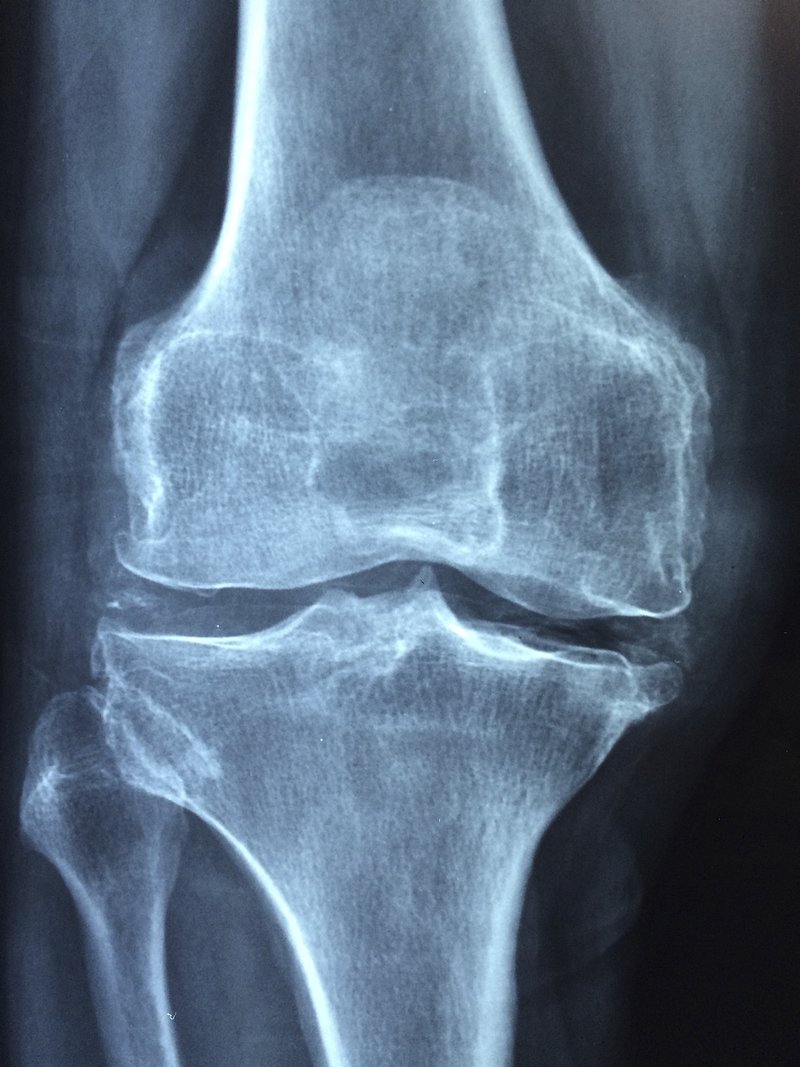

무릎통증 원인 4가지

무릎통증 원인은

대개 어떤것들이 있을까요

일반적인 경우엔 이런것들이 있습니다.

(1) 근육 염좌

(2) 연골 혹은 반월상 연골판 파열

(3) 관절염

(4) 대퇴-슬개 관절 아픔

이런

경우가 대부분의 원인으로 꼽힌다고 할 수 있습니다.

무릎통증 치료방법

무릎통증 치료방법은 어떤게 있을까요?

무릎 관절을 치료할 땐 우선 약물치료, 물리 치료 및 무릎 주위 근육을 강화하는

재활 치료 등 기본적인 초기 치료를 진행한다.

반월상연골 파열로 의심되는 경우 자기공명영상(MRI) 검사로 진단할 수 있다.

초기라면 관절 기능 개선에 도움을 줄 수 있는 보존적 치료로 호전을 기대할 수 있다.